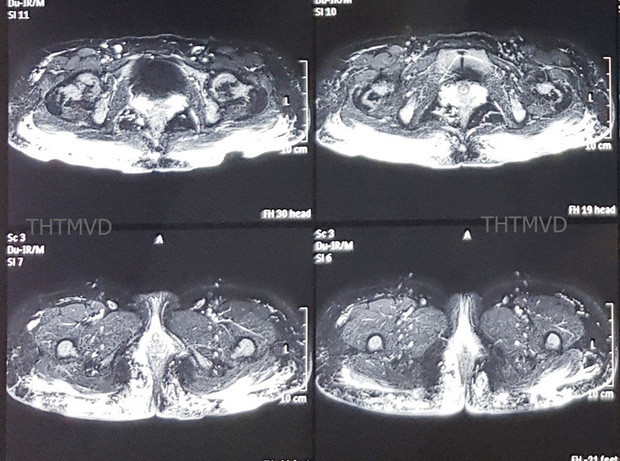

| Hình ảnh vùng mông có nhiều khối u siliconoma- Ảnh: Bác sĩ cung cấp. |

Trên phim chụp cộng hưởng từ cho thấy hàng trăm khối u siliconoma (sau bơm silicone bạch cầu gom lại thành khối) cùng hiện tượng viêm lan tỏa trong lớp da cơ mông và thâm nhiễm cả đến gần hậu môn. Đáng nói là khi cấy mủ vùng mông, các bác sĩ phát hiện bệnh nhân đã bị nhiễm loại vi khuẩn đa kháng thuốc, kháng hầu hết các loại kháng sinh thông thường.